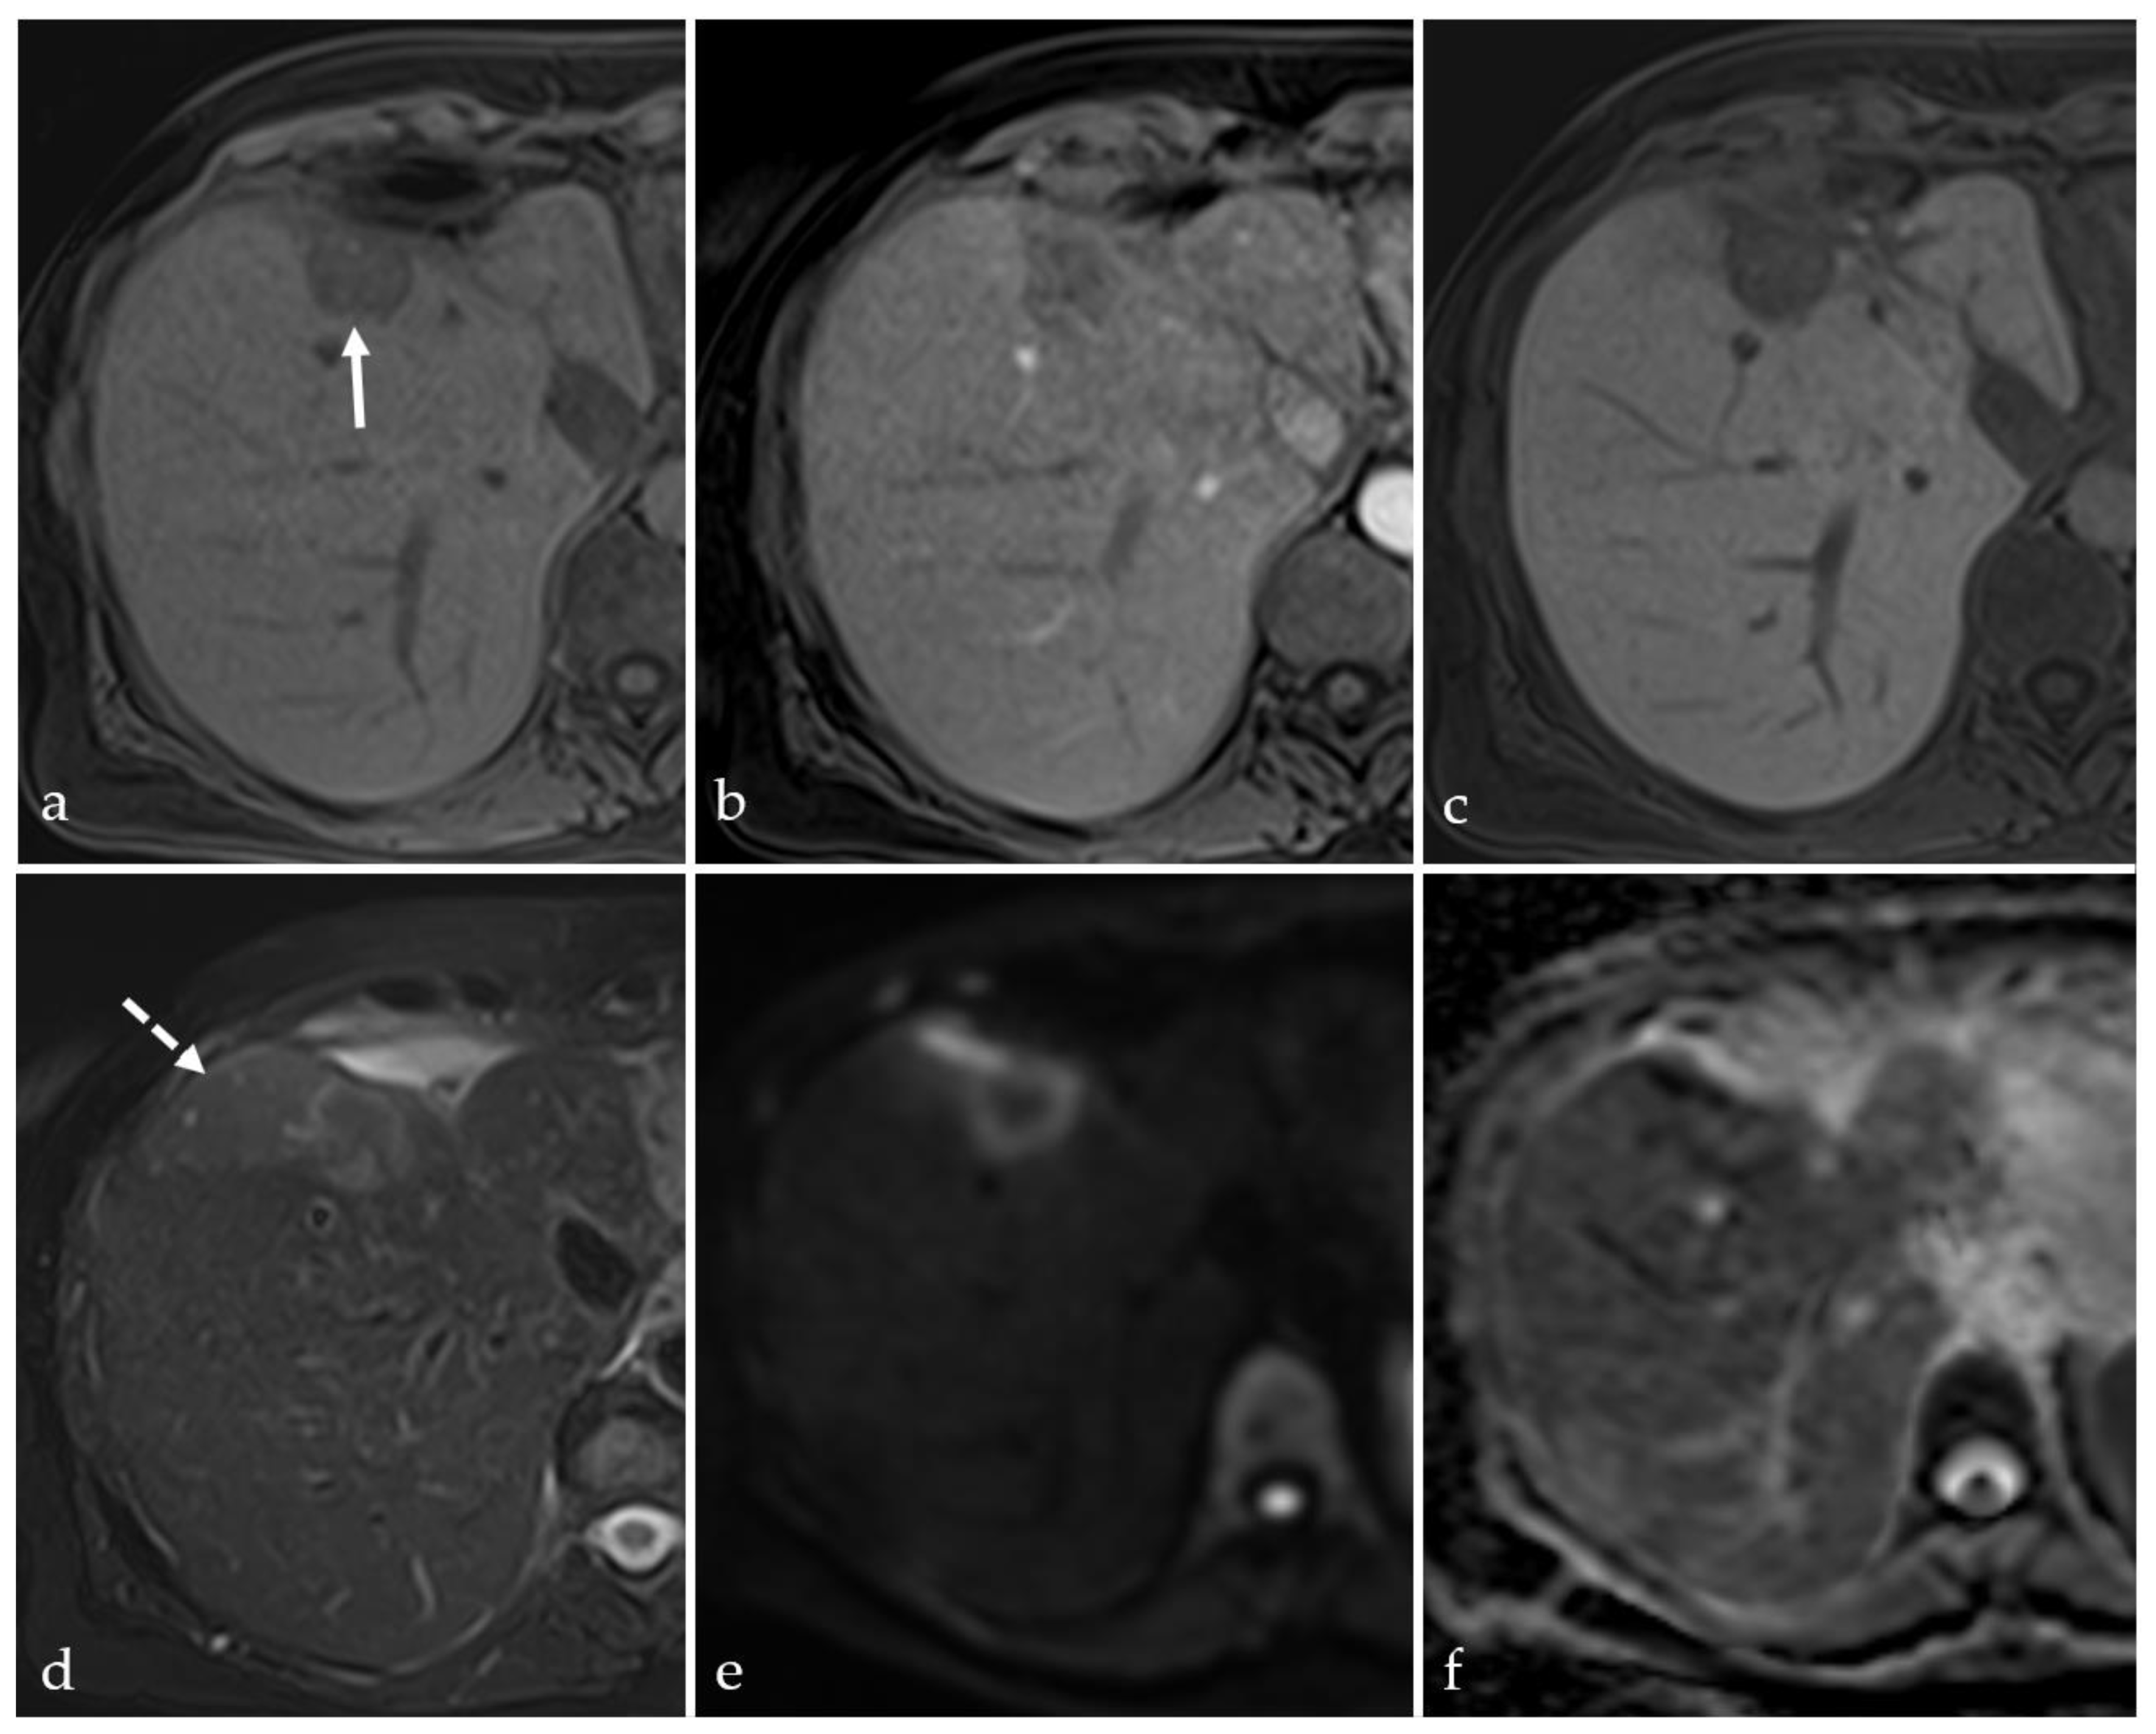

3.5. Post-Treatment Imaging Features of Tumor Viability

3.6. Current and Future Perspectives in Targeting Tumor Nodules